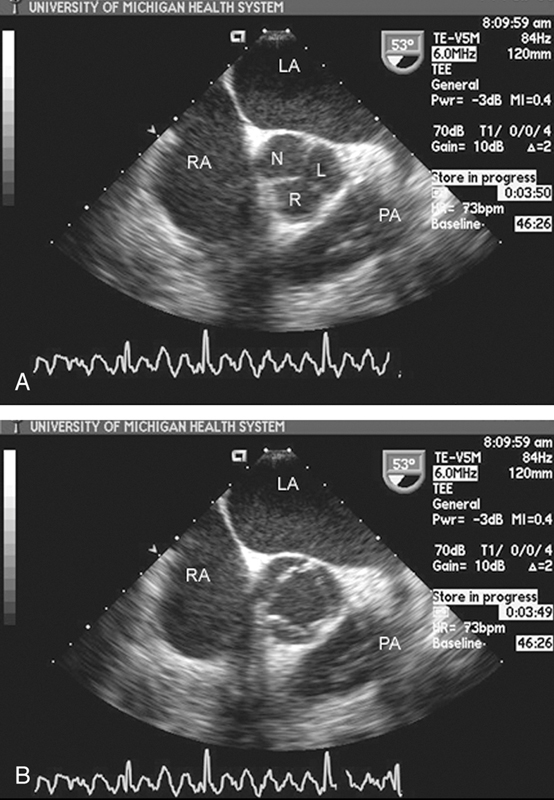

فحوصات تشخيصية لبعض امراض القلب والشرايين التاجية